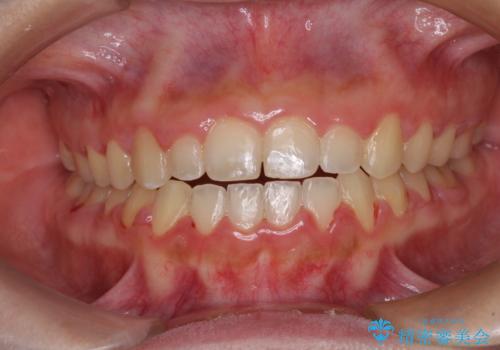

上顎骨を拡大したことで、下顎の歯列を上顎が受け入れられるようになりましたが、インビザラインでは咬み合わせを改善させることができなかったため、ワイヤー矯正にて仕上げることとしました。

ワイヤーを使用したものの、上下前歯のオープンバイトがなかなか改善されませんでしたが、患者希望により治療終了となりました。